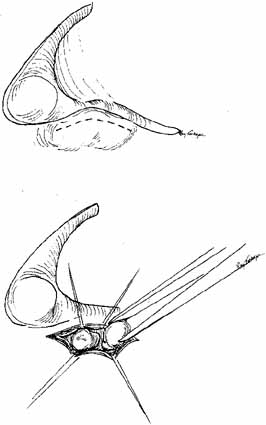

with Silastic intubation has a high success rate. Silastic Intubation of the Nasolacrimal Duct The major difficulty in dealing with persistent dacryocystostenosis is

deciding how to proceed if all of these measures fail. Before progressing

to the more aggressive DCR,22,62–67 a secondary procedure should be considered like passing Silastic tubing

through the entire nasolacrimal system into the nose (Fig. 21). Although Silastic intubation of the nasolacrimal system appears

to be a more conservative and reasonable approach, it can be a traumatic

procedure, especially in a young child. Therefore, caution is essential

to minimize complications. Furthermore, the procedure is not indicated

for bony obstruction or severe scarring from previous procedures. In

addition to Silastic intubation, balloon dacryoplasty of the nasolacrimal

duct is a viable secondary option.  Fig. 21 Silastic tubing is placed through the entire nasolacrimal system. Fig. 21 Silastic tubing is placed through the entire nasolacrimal system.